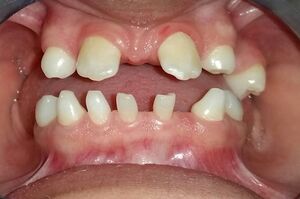

Anodontia view of patient showing oligodontia and conical teeth

Congenital absence of permanent teeth can present as hypodontia, usually missing one or two permanent teeth, or oligodontia that is the congenital absence of six or more teeth. Congenital absence of all wisdom teeth, or third molars, is relatively common. Anodontia is the congenital absence of teeth and can occur in some or all teeth; whereas partial anodontia (or hypodontia), involves two dentitions or only teeth of the permanent dentition (Dorland's 1998). Approximately 0.08-0.25% of the population has oligodontia.[1] Many denominations are attributed to this anomaly: partial anodontia, hypodontia, oligodontia, the congenital absence, anodontia, bilateral aplasia. Anodontia being the term used in controlled vocabulary Medical Subject Headings (MeSH) from MEDLINE which was developed by the United States National Library of Medicine. The congenital absence of at least one permanent tooth is the most common dental anomaly and may contribute to masticator dysfunction, speech impairment, aesthetic problems, and malocclusion (Shapiro and Farrington 1983). Absence of lateral incisors represents a major stereotype. Individuals with this condition are perceived as socially most aggressive compared with people without anodontia (Shaw 1981).[2] The occurrence of anodontia is less so than hypodontia which has a prevalence of 0.1-0.7% in primary teeth and 3–7.5% in permanent teeth.[3]

Hypodontia and anodontia are frequently associated with a multitude of genetic disorders and syndromes, approximately 70. Syndromes particularly involved with ectodermal involvement are a prime circumstance for anodontia to occur, some examples of these are: Rieger's, Robinson's and focal dermal hypoplasia. Three syndromes which classically have signs of anodontia are oculomandibulodyscephaly, mesoectodermal dysplasia and ectodermal dysplasia. In cases of oculomandibulodyscephaly there are no permanent teeth but there are deciduous teeth present. In mesoectodermal dysplasia the symptoms are anodontia and hypodontia. In cases of ectodermal dysplasia oligodontia is also present. Other symptoms associated with anodontia include: Alopecia, loss of sweat glands, cleft lip or palate, or missing finger nails.[4]

Anodontia can be diagnosed when a baby does not begin to develop teeth around the age of 12 to 13 months or when a child does not develop their permanent teeth by the age of 10. The dentist can use a special X-ray, such as a panoramic image, to check if there are any teeth developing. There is also a higher risk for a child to develop anodontia if their parent has this disorder as well. In the absence of all permanent teeth, anodontia will be diagnosed. If between one and five teeth are missing, this will be diagnosed as hypodontia. In the absence of six or more teeth, this will be diagnosed as oligodontia.[4]